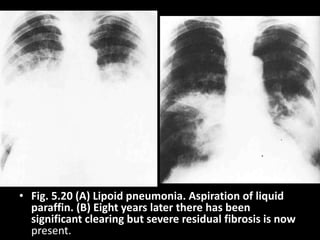

• Fig. 5.20 (A) Lipoid pneumonia. Aspiration of liquid

paraffin. (B) Eight years later there has been

significant clearing but severe residual fibrosis is now

present.

• Fig. 5.20(A) Lipoid pneumonia. Aspiration of liquid paraffin. (B) Eight years later there has been significant clearing but severe residual fibrosis is now present.